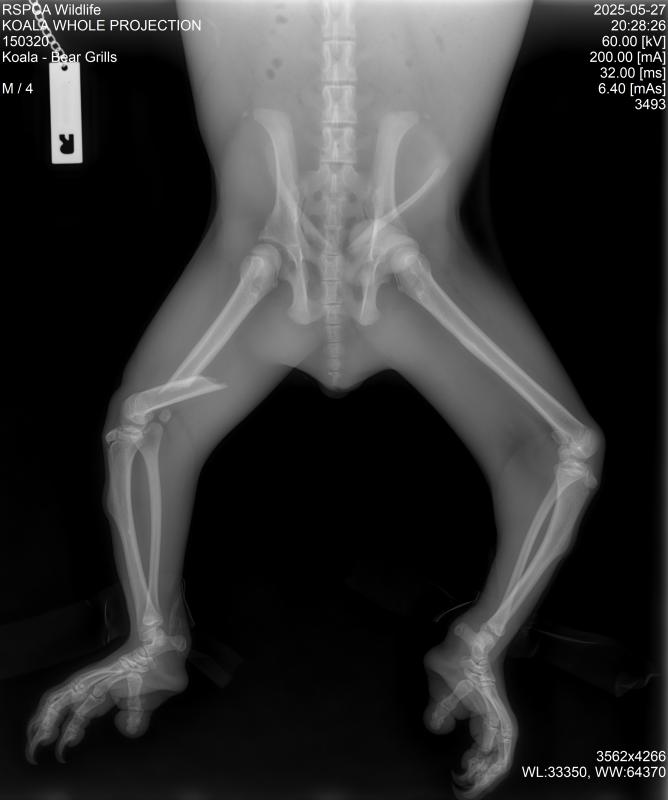

Photo of an x-ray showing the extent of Bear’s injuries.

An x-ray showing the extent of Bear’s injuries. Photo: RSPCA Queensland.

“I’m pleased to report that Bear Grills is healthy and recovering well after undergoing surgery for a fractured thigh,” Ms Colbran said.